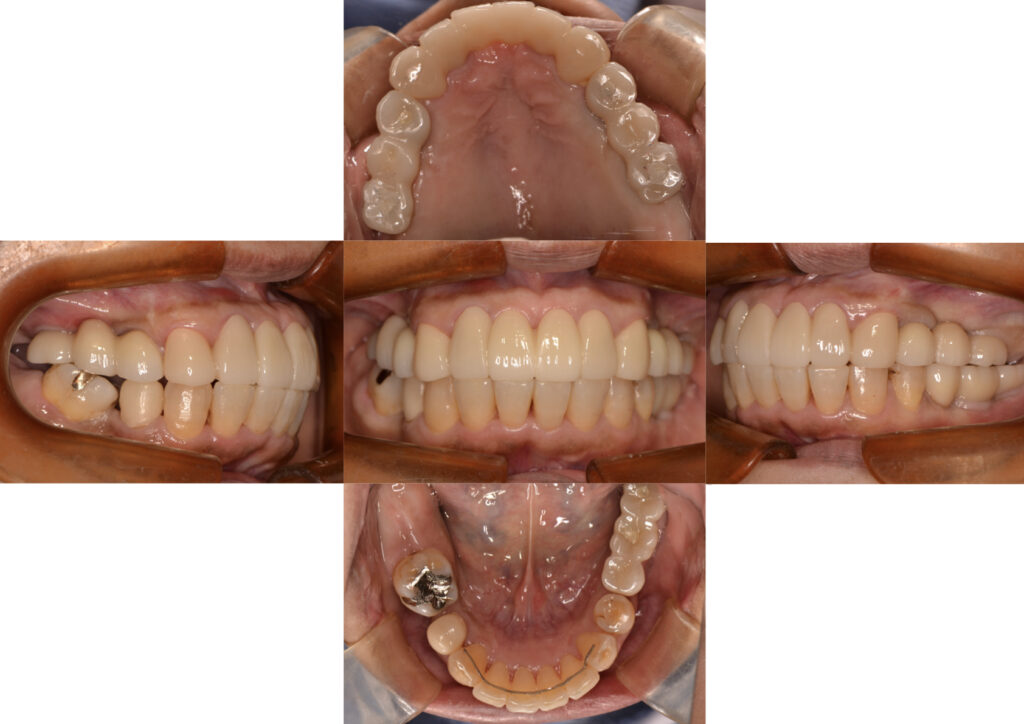

1年2ヶ月後の治療完了時。完全な理想咬合の回復とまではいきませんが、できるだけ患者さんの身体的苦痛や経済的負担を最小限にとどめた中で最大限の機能と審美の回復ができたかと思います。